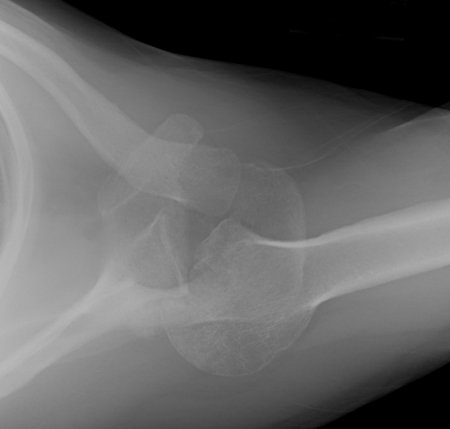

Anteroposterior x-ray view of an elbow dislocation

Personal collection of Dr Paul Novakovich